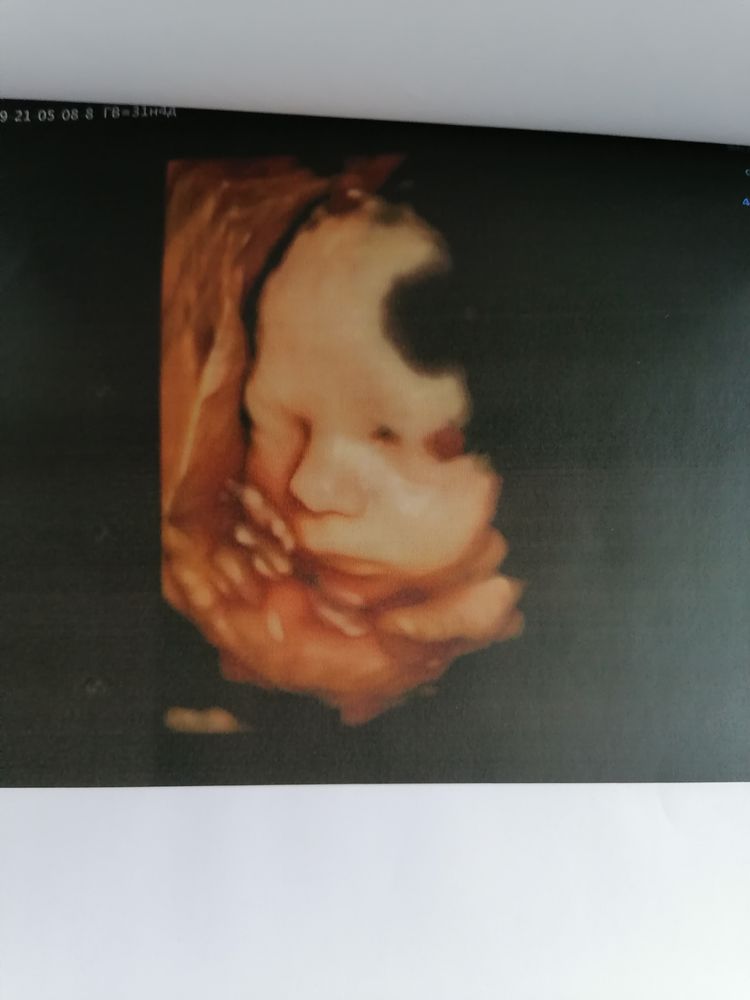

Ну а теперь о сегодняшнем скрининговом узи в 31.4 недели у Пятых Н. С.

Всё как обычно отлично, ощущение, что она нас помнит, все расспросила перед узи, пообщались. Вообщем мы с мужем довольны на все 200%. Очень тщательно рассмотрела каждый орган сыночка. Долго пытались его развернуть что бы увидеть личико и у нас получилось. Включала 4Д узи ждали пока он улыбнётся и опять таки дождались🥰.

По узи с сыночком все тттттт отлично, растёт чётко в срок, уже нет опережение. Все органы на месте, все с ними хорошо. Врач сказала, что очень большие кулачки и ножки🙈. Да я и сама видела, прям такая мужицкая рука и чувствую ух как эти кулачки и ножки🥰.

Весит 1890, что норма для 31.5 недели.

Ну и фоточки сыночка 👶🙏🙏🙏🥰. Люблю его сил нет❤️❤️❤️

Улыбашка мой